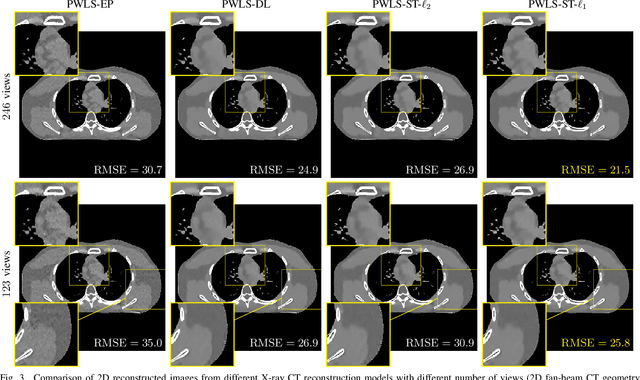

A major challenge in X-ray computed tomography (CT) is reducing radiation dose while maintaining high quality of reconstructed images. To reduce the radiation dose, one can reduce the number of projection views (sparse-view CT); however, it becomes difficult to achieve high quality image reconstruction as the number of projection views decreases. Researchers have applied the concept of learning sparse representations from (high-quality) CT image dataset to the sparse-view CT reconstruction. We propose a new statistical CT reconstruction model that combines penalized weighted-least squares (PWLS) and $\ell_1$ regularization with learned sparsifying transform (PWLS-ST-$\ell_1$), and an algorithm for PWLS-ST-$\ell_1$. Numerical experiments for sparse-view 2D fan-beam CT and 3D axial cone-beam CT show that the $\ell_1$ regularizer significantly improves the sharpness of edges of reconstructed images compared to the CT reconstruction methods using edge-preserving regularizer and $\ell_2$ regularization with learned ST.